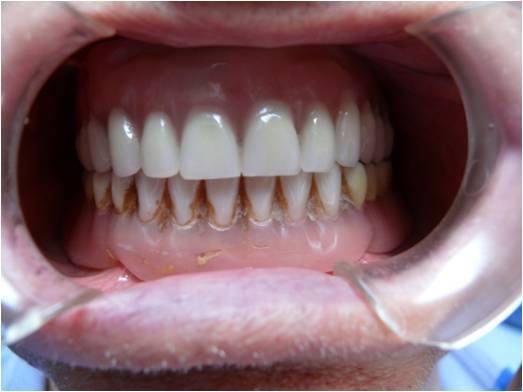

Diagnosi e trattamento tumori benigni e maligni del cavo orale

Il paziente al quale viene clinicamente evidenziata una lesione sospetta del cavo orale viene sottoposto in tempi brevi a prelievo bioptico ed esame istopatologico per una certezza diagnostica. In casi di conferma di patologia tumorale, a seconda della gravità , sarà trattato chirurgicamente in anestesia generale presso i nosocomi di Jesi o Fabriano oppure inviato attraverso canali preferenziali presso un centro di riferimento di chirurgia maxillo-facciale.